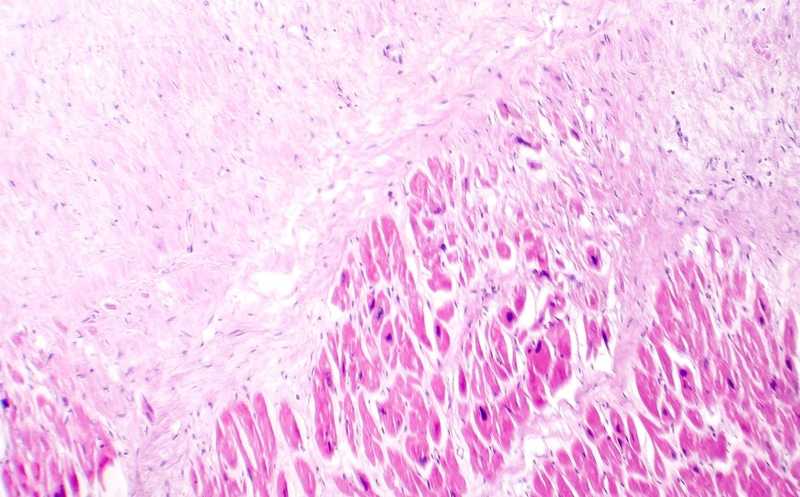

Сначала исследователи провели анализ пространственной транскриптомики сердца мыши, в кардиомиоцитах которого искусственно активировали YAP5SA. Проведя секвенирование РНК единичных клеток, они обнаружили семь клеточных категорий: взрослые кардиомиоциты двух типов (aCM1 и aCM2), гладкомышечные клетки, фибробласты сердца, макрофаги и два типа эндотелиальных клеток (EC1 и EC2). В сердцах с активацией YAP5SA количество макрофагов и aCM2 увеличивалось, а EC2 — уменьшалось. Математическое моделирование экспрессии выявило модуль из 62 генов, коррелировавший с переходом от aCM1 к aCM2. Часть этих генов была ассоциирована с разборкой саркомеров.

Дальнейшее сравнение между aCM1 и aCM2 показало, что во втором типе кардиомиоцитов активнее экспрессировались фетальные гены, в том числе связанные с организацией саркомеров. Экспрессия генов окислительного метаболизма, напротив, была снижена в aCM2. Исходя из этого, ученые предположили, что aCM2 представляет собой фетальную популяцию кардиомиоцитов.

Из 346 генов, экспрессия которых повышалась в содержащих aCM2 участках сердца, восемь относились к системе комплемента (Cfh, Apoe, Serping1, C3, C1qb, C1qc, C1qa и Clu). При этом C3 экспрессировался в фибробластах aCM2-содержащих участков, а С1 — в макрофагах той же локализации. Эти макрофаги экспрессировали также рецептор к C3 (С3ar1). Такую колокализацию aCM2, C3+ фибробластов и C3ar1+ макрофагов авторы обозначили как клеточные триады.